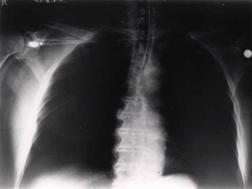

TRAUMATISME TORACICE

Emfizem subcutanat

Emfizem subcutanat Emfizem subcutanat

Aspect radiologic Imagine CT